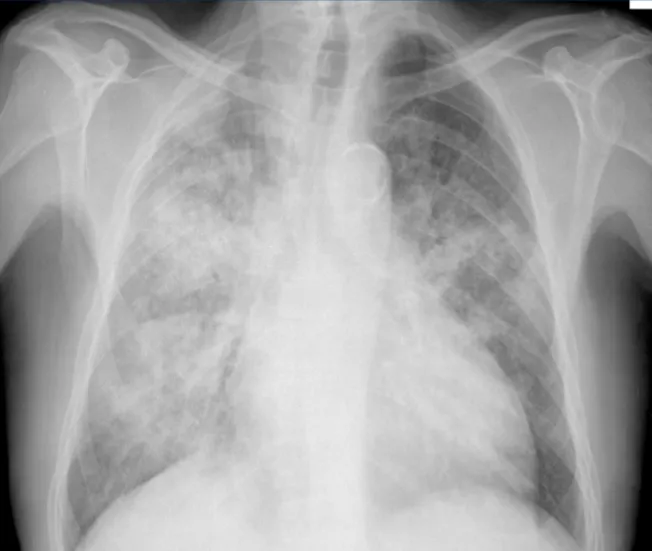

Pneumocystis jirovecii Pneumonia (PJP)

- Sx: Insidious fever, tachypnea, dyspnea, non-productive cough, hypoxia.

- CXR: Bilateral interstitial infiltrates ('ground-glass').

- Dx: Organism in BAL/sputum. LDH ↑.

- Rx: TMP-SMX (21 days). Steroids if PaO2 < 70mmHg.

- Prophylaxis: TMP-SMX. 📌 PJP: Pneumo Jiroveci = Just Juice (TMP-SMX).